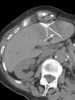

Metastatic ovarian cancer